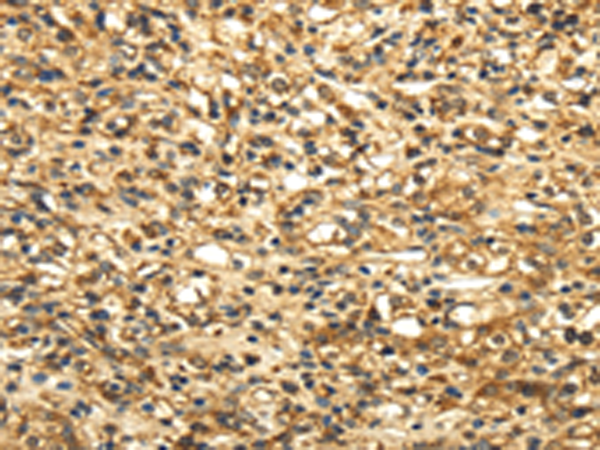

分类: 科研抗体货号: P12173别名:应用: IHC反应种属: Human, Mouse